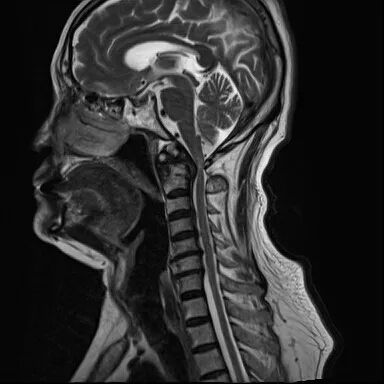

▲术前

此次接受手术的患者年事已高,基础疾病较多,身体耐受度低、手术风险显著高于普通患者。若保守治疗,脱位难以复位,脊髓压迫持续加重;若手术治疗,则对术者精准操作、麻醉管理、围手术期护理均提出极高要求。